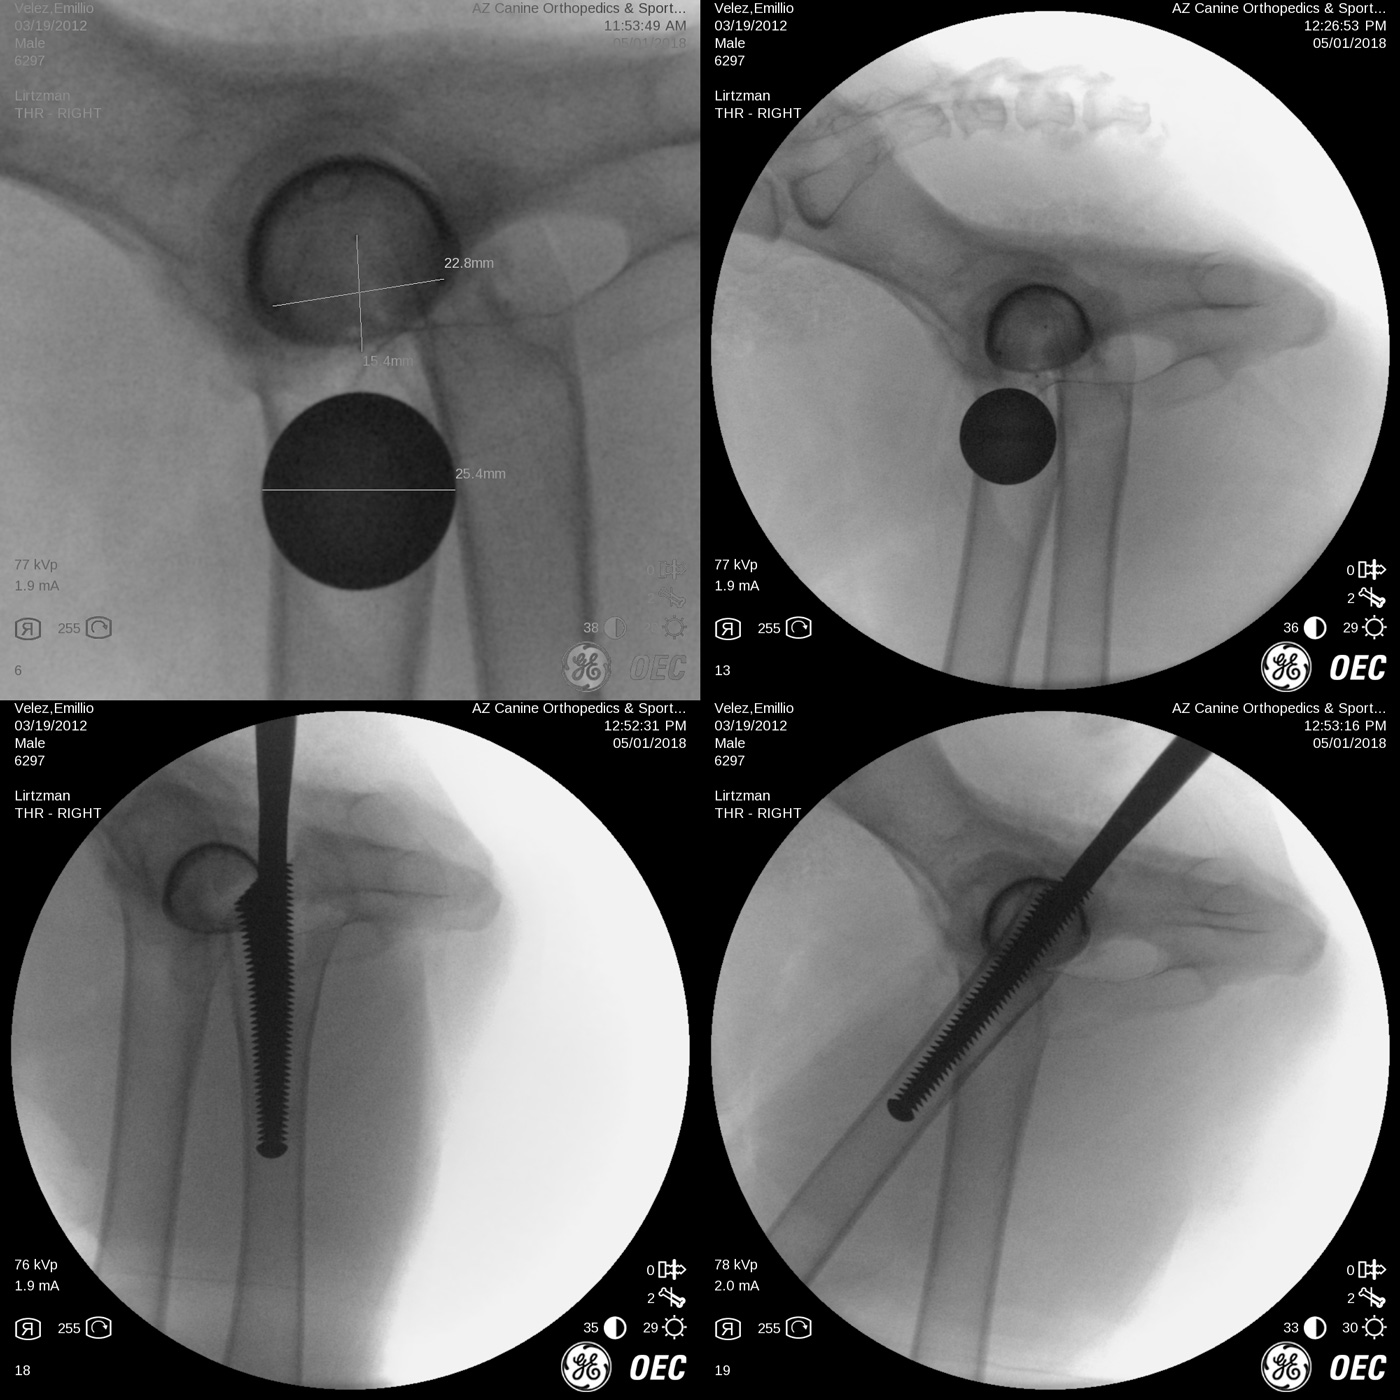

Risk associated with patient malpositioning or movement of the pelvis during surgery, bone preparation techniques, implant sizing and implant postion-orientation have been greatly reduced by the addition of intra-operative x-ray imaging as seen below. The most common and significant problems include:

This is an example of a German Shepherd dog with bilateral, hybrid, total hip replacement (Biomedtrix BFX cementless acetabular cup and CFX cemented femoral stem). Hybrid constructs may be used in certain breeds like the German Shepherd and giant breed dogs, geriatric dogs or those with poor bone quality/thin femoral cortices.